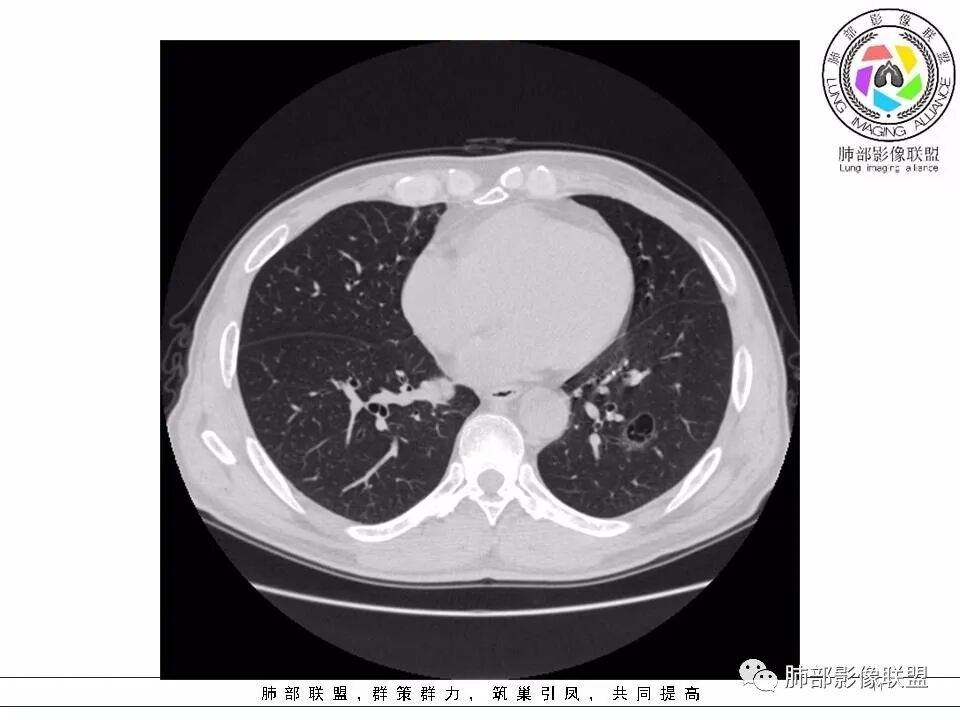

2.左肺下叶外基底段囊腔样病灶,轮廓柔和,壁厚薄不均,见壁结节。内见分隔或脊状突起。腔内见血管穿行。

这是有“故事”的囊!

3.囊壁外环以磨玻璃影,边界较清楚。

1.囊腔壁厚薄不均,壁结节,内有分隔,其内有血管穿行,指向新生物。

2.临近有边界清楚磨玻璃影,指向腺癌。